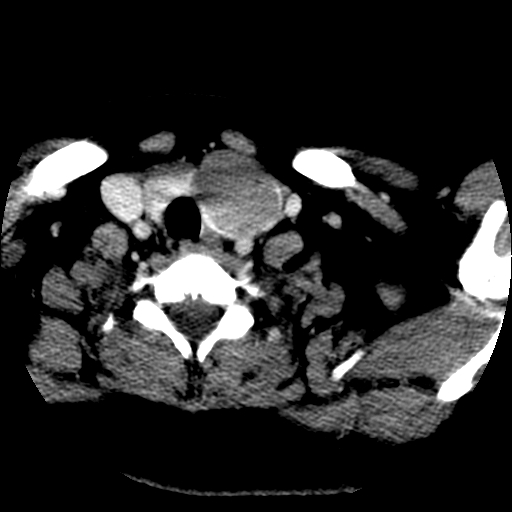

标题: CT25491:女,55岁,发现左侧甲状腺肿块一个月。 [打印本页]

标题: CT25491:女,55岁,发现左侧甲状腺肿块一个月。

女,55岁,发现左侧甲状腺肿块一个月,彩超示:甲状腺多发结节伴左叶结节液化。